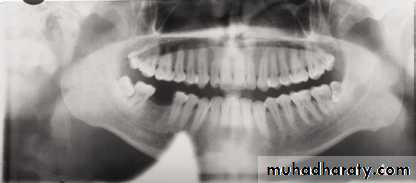

Metallic bone plates used for fixation of a fracture of the left side of the mandible